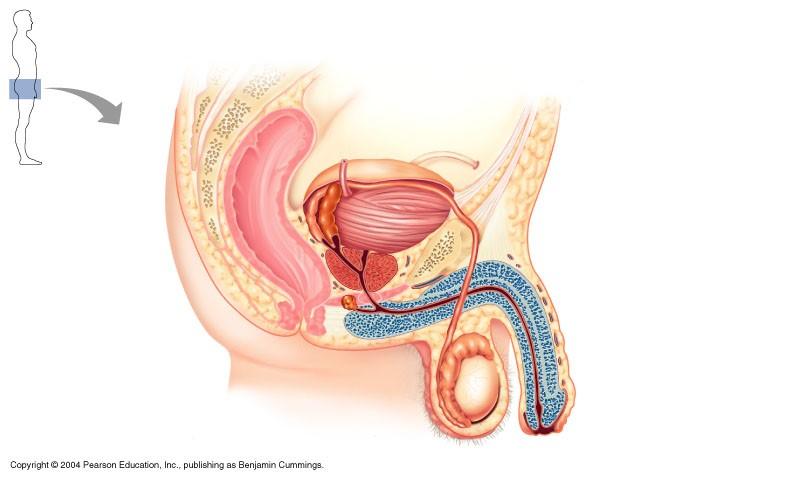

The structure indicated in the diagram of male reproductive system is

Vas deferens

Which is the most correct sequence of sperm flow in the male duct system

seminiferous tubules, epididymis, vas deferens, ampulla, ejaculatory duct, urethra

The structure indicated in the diagram below of the male reproductive system is

epididymis

The structure indicated in the diagram of the male reproductive system is the ejaculatory duct

The structure indicated in the diagram of male reproductive system is epididymis

Male reproductive system

ampulla of ductus deferens

vas deferens

prostate

epididymis

testes

male reproductive structure